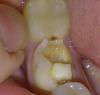

Linti Опубликовано 17 января, 2010 Поделиться Опубликовано 17 января, 2010 Мне депульпировали зуб нижнюю 5 достаточно давно и вот недавно он разрушился.Врач в гос.полликлинике посоветовала вкладку+коронку. Права ли она? Очень хочется спасти то, что осталось... Если это вариант, то что лучше ставить из бюджетного, но надежного(если знаете клинику, то буду признательна). И постепенно на все депульпированные поставлю вкладки и коронки. Так что информация очень нужна.Зуб этот не видно при улыбке, только если хохотать и специально в рот заглядывать, поэтому об эстетике сейчас не говорю. Фото зуба прилагаю P.S.Никогда в жизни до сегодняшнего не знала что их надо укреплять коронками. Хотя зуб о котором идет речь лечила в частной клинике. И могу ли я месяц проходить с этим 5 зубом вот так, а то пока денег не очень. И последнее, я так понимаю, что все это ставится поэтапно, значит и оплата поэтапная. Если не трудно напишите, пожалуйста, об этапах. Заранее спасибо за советы Ссылка на комментарий

Большой Зеленый Опубликовано 17 января, 2010 Поделиться Опубликовано 17 января, 2010 Мне депульпировали зуб нижнюю 5 достаточно давно и вот недавно он разрушился.Врач в гос.полликлинике посоветовала вкладку+коронку. Права ли она? Очень хочется спасти то, что осталось... Если это вариант, то что лучше ставить из бюджетного, но надежного(если знаете клинику, то буду признательна). И постепенно на все депульпированные поставлю вкладки и коронки. Так что информация очень нужна.Зуб этот не видно при улыбке, только если хохотать и специально в рот заглядывать, поэтому об эстетике сейчас не говорю. Фото зуба прилагаю P.S.Никогда в жизни до сегодняшнего не знала что их надо укреплять коронками. Хотя зуб о котором идет речь лечила в частной клинике. И могу ли я месяц проходить с этим 5 зубом вот так, а то пока денег не очень. И последнее, я так понимаю, что все это ставится поэтапно, значит и оплата поэтапная. Если не трудно напишите, пожалуйста, об этапах.Заранее спасибо за советы 1 Доктор права. Вкладка + коронка2 Месяц проходите легко . дольше не надо.3 С оплатой везде по разному в зависимости от клиники и региона цена очень варьирует4 Это не пятый ,а шестой зуб (46) Ссылка на комментарий